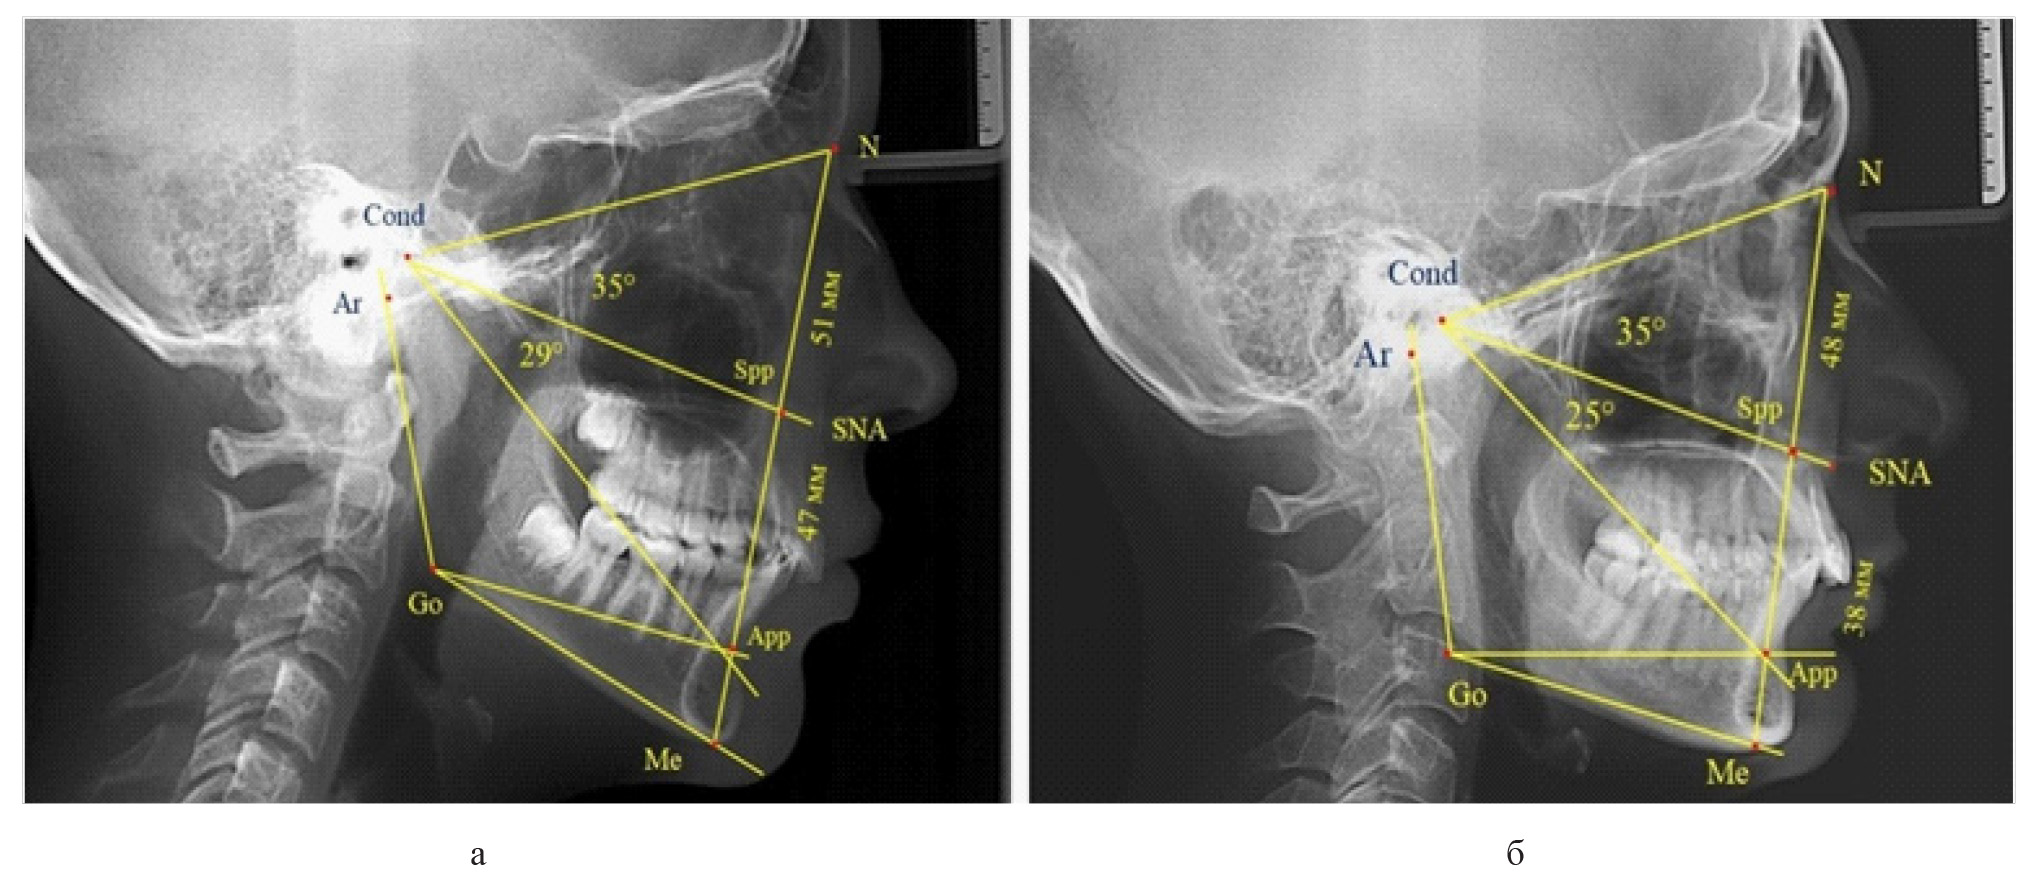

Признаки снижения высоты назального отдела вплоть до уровня горизонтального патологического типа при физиологической окклюзии были определены у 10 человек [(17,86 ± 5,11) %]. При этом параметры гнатического отдела соответствовали физиологической норме либо физиологическому горизонтальному типу (рис. 4).

Рис. 4. Варианты ТРГ с укороченными размерами носового отдела и оптимальными (а) и укороченными (б) размерами гнатической части